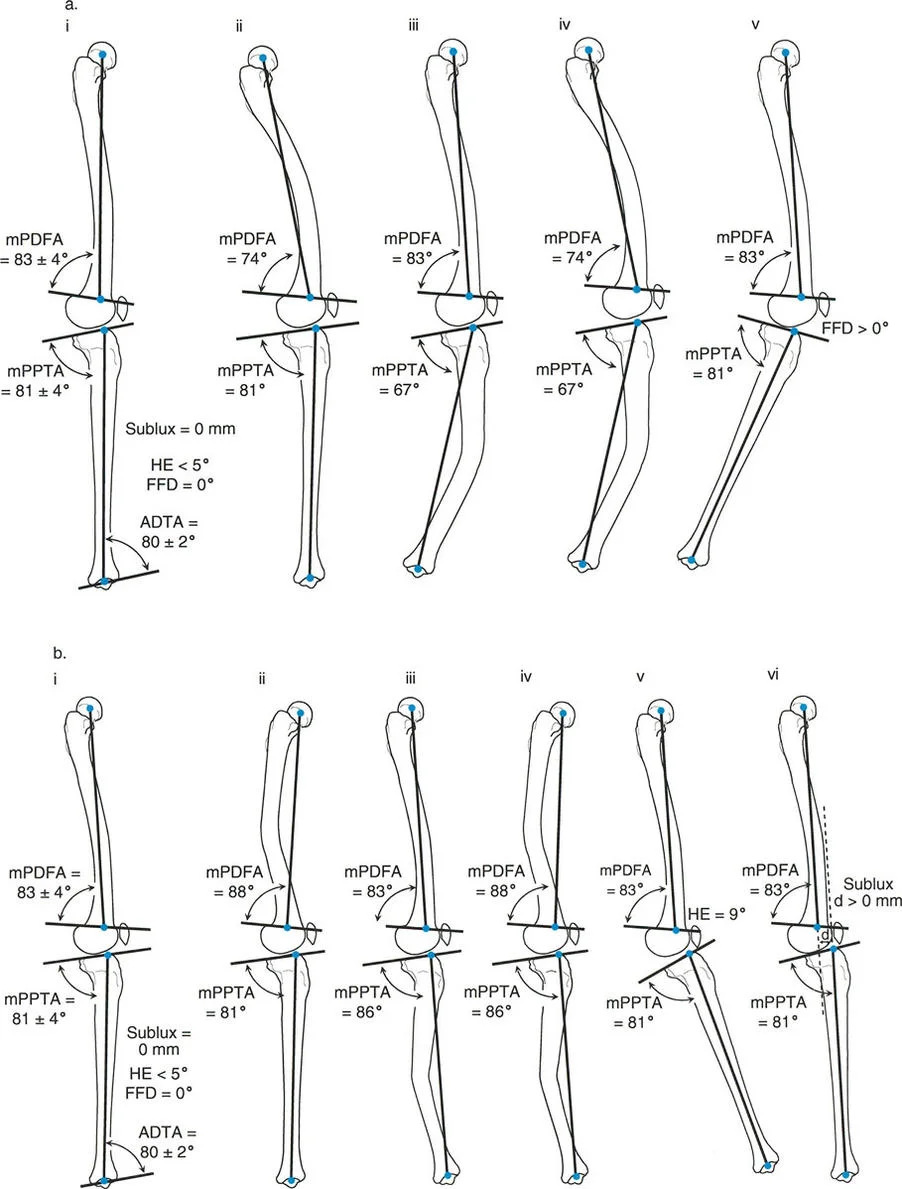

تثبيت المسمار الداخلي بمساعدة المثبت الخارجي (FAN) هو تقنية جراحية حديثة تجمع بين دقة المثبت الخارجي المؤقت واستقرار المسمار الداخلي الدائم، مما يوفر تصحيحًا فائقًا لتشوهات العظام المعقدة مع راحة فورية للمريض وتعافٍ أسرع.

الخلاصة الطبية السريعة: تثبيت المسمار الداخلي بمساعدة المثبت الخارجي (FAN) هو تقنية جراحية حديثة تجمع بين دقة المثبت الخارجي المؤقت واستقرار المسمار الداخلي الدائم، مما يوفر تصحيحًا فائقًا لتشوهات العظام المعقدة مع راحة فورية للمريض وتعافٍ أسرع.